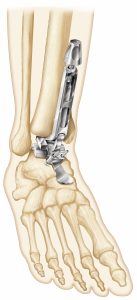

(Figure 4) Moreover, the Vantage tibial component’s central cage, similar to the cage featured on the Advita reverse total shoulder system, affords not only reliable press-fit fixation but adds the potential for bone ingrowth and superior long-term fixation.

(Figure 5) The instrumentation to prepare the tibia for vertical peg and cage orientation is unique and simple to use (Figure 6); the Advita engineering team was brilliant in creating this impaction system disproving many doubters, including myself, that such an impactor could be safely introduced despite the ankle joint’s relatively limited access. The Vantage talar component’s backside has a uniform curve that optimizes compressive forces on the prepared dome-shaped talus throughout the ankle’s full range of motion. In contrast, nearly all competitors’ talar components provide alarm component stability via chamfer cuts that tend to create the potential for shear stresses. (Figure 5) One recently released total ankle system, features a uniform dome-shaped talar preparation like that of the Vantage but requires a lateral approach and fibular osteotomy for component implantation. The Vantage’ talar component confers the same talar component advantages via the far more commonly used anterior approach and does not require a fibular osteotomy. Unique to the Vantage total ankle system, a simple manual rasp is used to complete the uniform talar dome preparation.

(Figure 7) Two anterior pegs designed to provide initial component stability do not detract from the uniformly compressive forces throughout the range of motion. The central talar component sulcus on the components articulating surface maintains the Vantage’s coronal plane stability for the polyethylene and ankle.

Based on the successful Advita total knee polyethylene implant, the Vantage’s polyethylene component, affords high fracture toughness and low wear rates. The polyethylene, with its congruent articulation on the talar component, affords satisfactory coronal plane ankle stability without creating undue constraint. (Figure 2) Unique to the Vantage fixed-bearing total ankle system is the locking clip technology that secures the polyethylene to the tibial tray. (Figure 8) Through exhaustive stress and cyclic load testing, the Vantage team of engineers confirmed that the locking clip maintains satisfactory polyethylene fixation to the tibial tray; yet, extraction is easy should the polyethylene need to be exchanged.